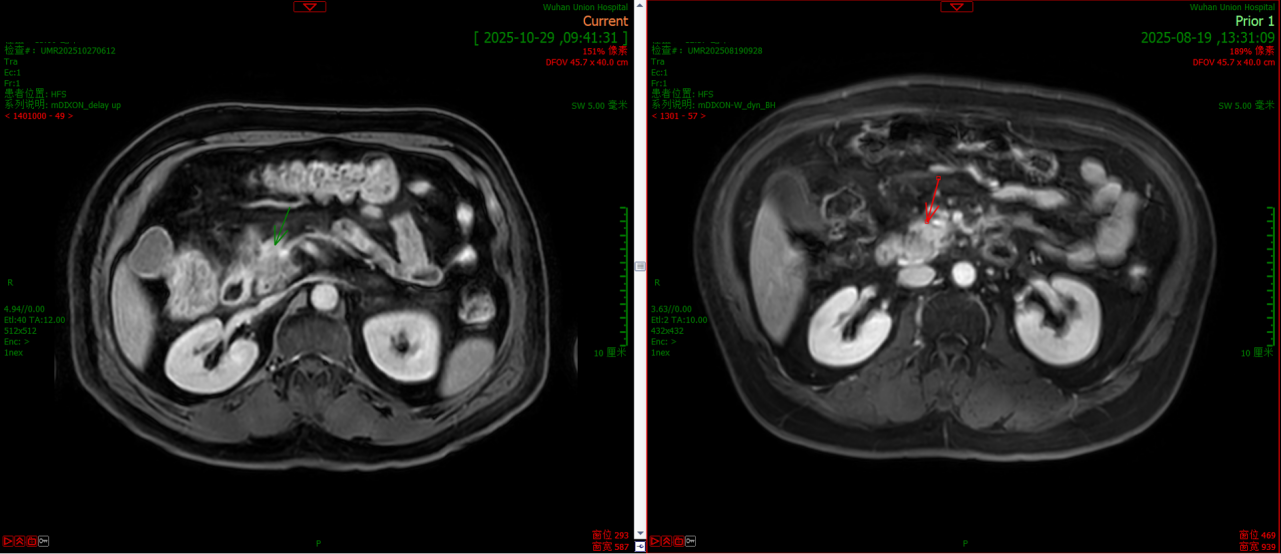

2025.08.20 腹部平扫+增强MRI:胰头、胰颈部病灶较大截面径约24x20mm。较院外前片比较,评价为部分缓解(PR)。

2025.10.29 腹部平扫+增强MRI:胰头、胰颈部病灶较大截面径约22x20mm。评价为疾病稳定(SD)。